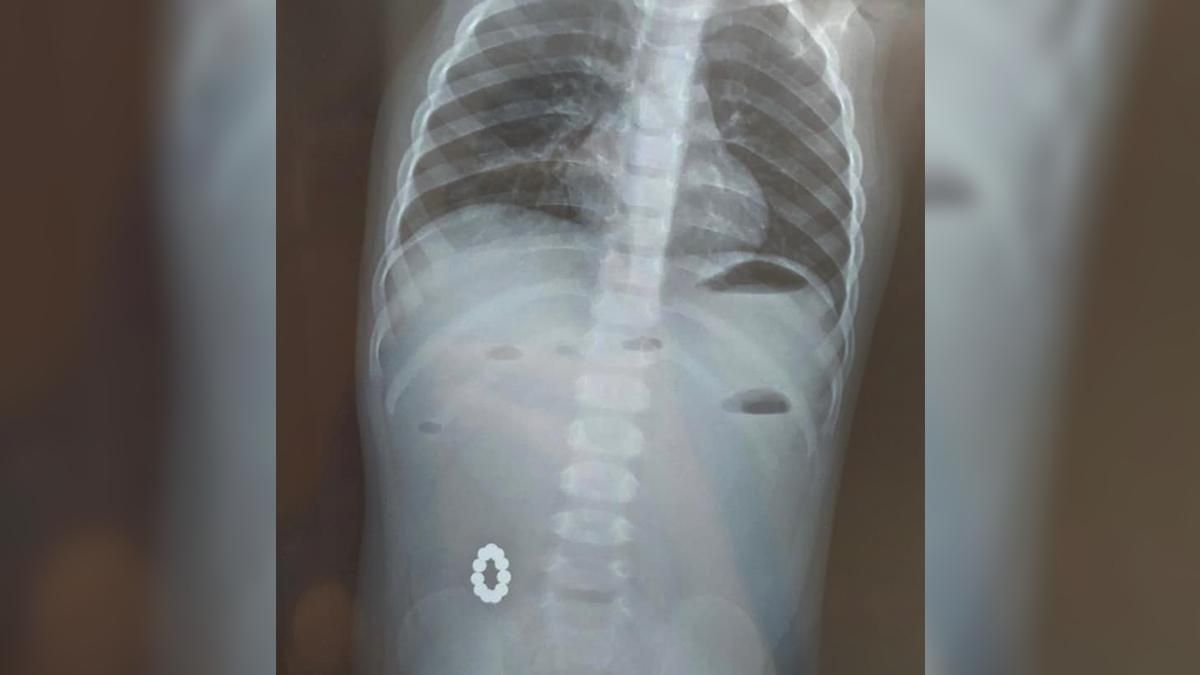

1-річну дівчинку привезли до лікарні з підозрою на харчове отруєння. Проте лікарі почали її обстежувати й виявили круглі магнітики, які були в кишківнику. Вони між собою з'єдналися та утворили кільце.

Магнітів, які лікарі дістали з малечі / Фото Харківської обласної дитячої лікарні №1

А саме - магніти, які між собою з'єдналися та утворили кільце.